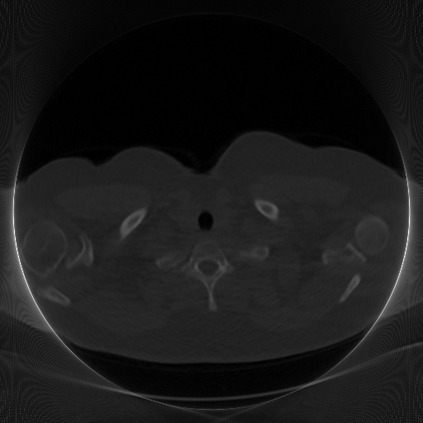

Low-Dose Computed Tomography (LDCT) technique, which reduces the radiation harm to human bodies, is now attracting increasing interest in the medical imaging field. As the image quality is degraded by low dose radiation, LDCT exams require specialized reconstruction methods or denoising algorithms. However, most of the recent effective methods overlook the inner-structure of the original projection data (sinogram) which limits their denoising ability. The inner-structure of the sinogram represents special characteristics of the data in the sinogram domain. By maintaining this structure while denoising, the noise can be obviously restrained. Therefore, we propose an LDCT denoising network namely Sinogram Inner-Structure Transformer (SIST) to reduce the noise by utilizing the inner-structure in the sinogram domain. Specifically, we study the CT imaging mechanism and statistical characteristics of sinogram to design the sinogram inner-structure loss including the global and local inner-structure for restoring high-quality CT images. Besides, we propose a sinogram transformer module to better extract sinogram features. The transformer architecture using a self-attention mechanism can exploit interrelations between projections of different view angles, which achieves an outstanding performance in sinogram denoising. Furthermore, in order to improve the performance in the image domain, we propose the image reconstruction module to complementarily denoise both in the sinogram and image domain.

翻译:降低对人体的辐射伤害的低剂量成像技术(LDCT)正在引起人们对医疗成像领域的兴趣。由于低剂量辐射导致图像质量下降,LDCT考试需要专门的重建方法或解密算法。然而,最近大多数有效方法忽略了原始投影数据的内部结构(Sintmag),这种数据限制了它们的分泌能力。罪状的内结构是罪状图领域数据的特殊特征。通过在解密的同时保持这一结构,噪音可以明显地受到限制。因此,我们建议使用Singraph Inner-Strockre变异器(SIST)来降低图像质量网络的噪音,以便利用罪状领域的内部结构来减少噪音。具体地说,我们研究染色学的CT成像机制和统计特征来设计罪状内结构损失,包括恢复高质量CT图像的全球和地方内部结构。此外,我们提议使用一种罪状变形模型模块来更好地提取罪状特征。因此,我们提议使用一种自我观察的变形结构,在罪状模型中可以利用一种杰出的域域图的性变图,从而改进了不同图像的成图。